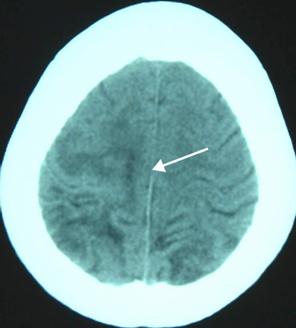

这一次,比在南昌好的是,终于查到了病因——父子两人其实并不是得了什么脑瘤,而是——中枢神经系统裂头蚴病。简单说,是一种寄生虫病,就是他们某次吃的青蛙里有一种叫裂头蚴的寄生虫进入了他们的身体,并随着血液进入了大脑,然后产生了如喷射状呕吐、抽搐、昏厥、癫痫等症状。

找到病因后,治疗相对来说就简单一些——做手术,将在脑子里的寄生虫取出来。于是,两个脑部手术,一下让我的邻居家成了赤贫状态,虽然邻里也会慰问一些,但终究杯水车薪。而最让人遗憾的是,手术后,脑部创伤是永久性且不可逆的,所以癫痫成为了他们伴随一生的痛。